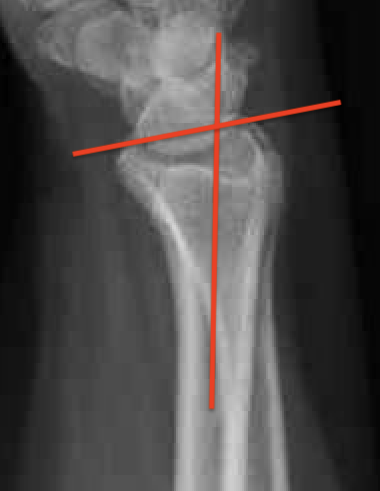

Distal Radius Angles

- radial volar tilt 11°

- radial inclination 22°

- radius is 11 mm longer than ulna

4. Radial inclination < 15o

5. Sagittal tilt

- > 15o dorsal

- > 20o volar